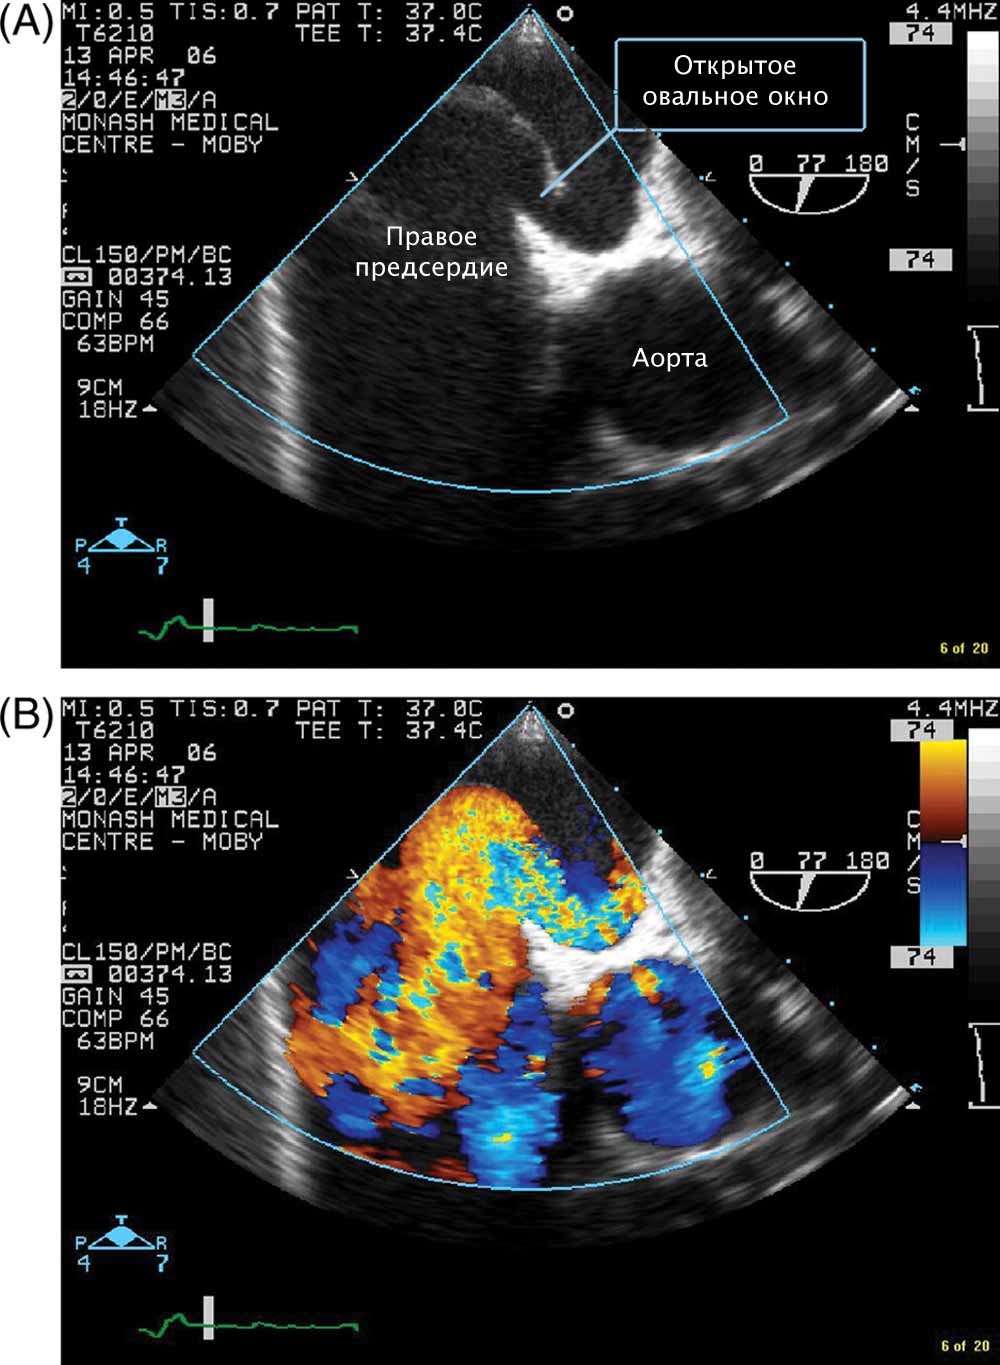

Чрезпищеводная эхокардиография

. Также дает возможность рассмотреть состояние овального окошка и измерить его пропускные свойства. Помимо этого, ЧПЭхоКГ позволит провести дифференциальную диагностику между аномальным развитием окошка и настоящим пороком развития перегородки между предсердиями. Этим методом также можно выявить начинающиеся осложнения патологии.

Как осуществляется контроль за выполнением эндоваскулярного вмешательства?

Достаточно часто требуется уточнение строения дефекта, тогда на этом этапе выполняют ангиографию – рентгеноконтрастное исследование сосудов. Окклюдер подбирают индивидуально, его помещают в катетер и доводят до сердца. Затем, под контролем с помощью видеоизображений, производится установка и раскрытие окклюдера.

Если требуется дополнительный контроль над работой сердца, то используют эхокардиограф с датчиком, помещаемым в пищевод. Чреспищеводная Эхокардиография позволяет наблюдать за состоянием сердечной мышцы в режиме реального времени.